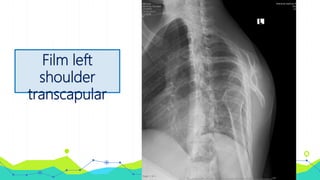

Film left

shoulder

transcapular

Investigation • Film leftshoulder AP • Film left shoulder transcapular